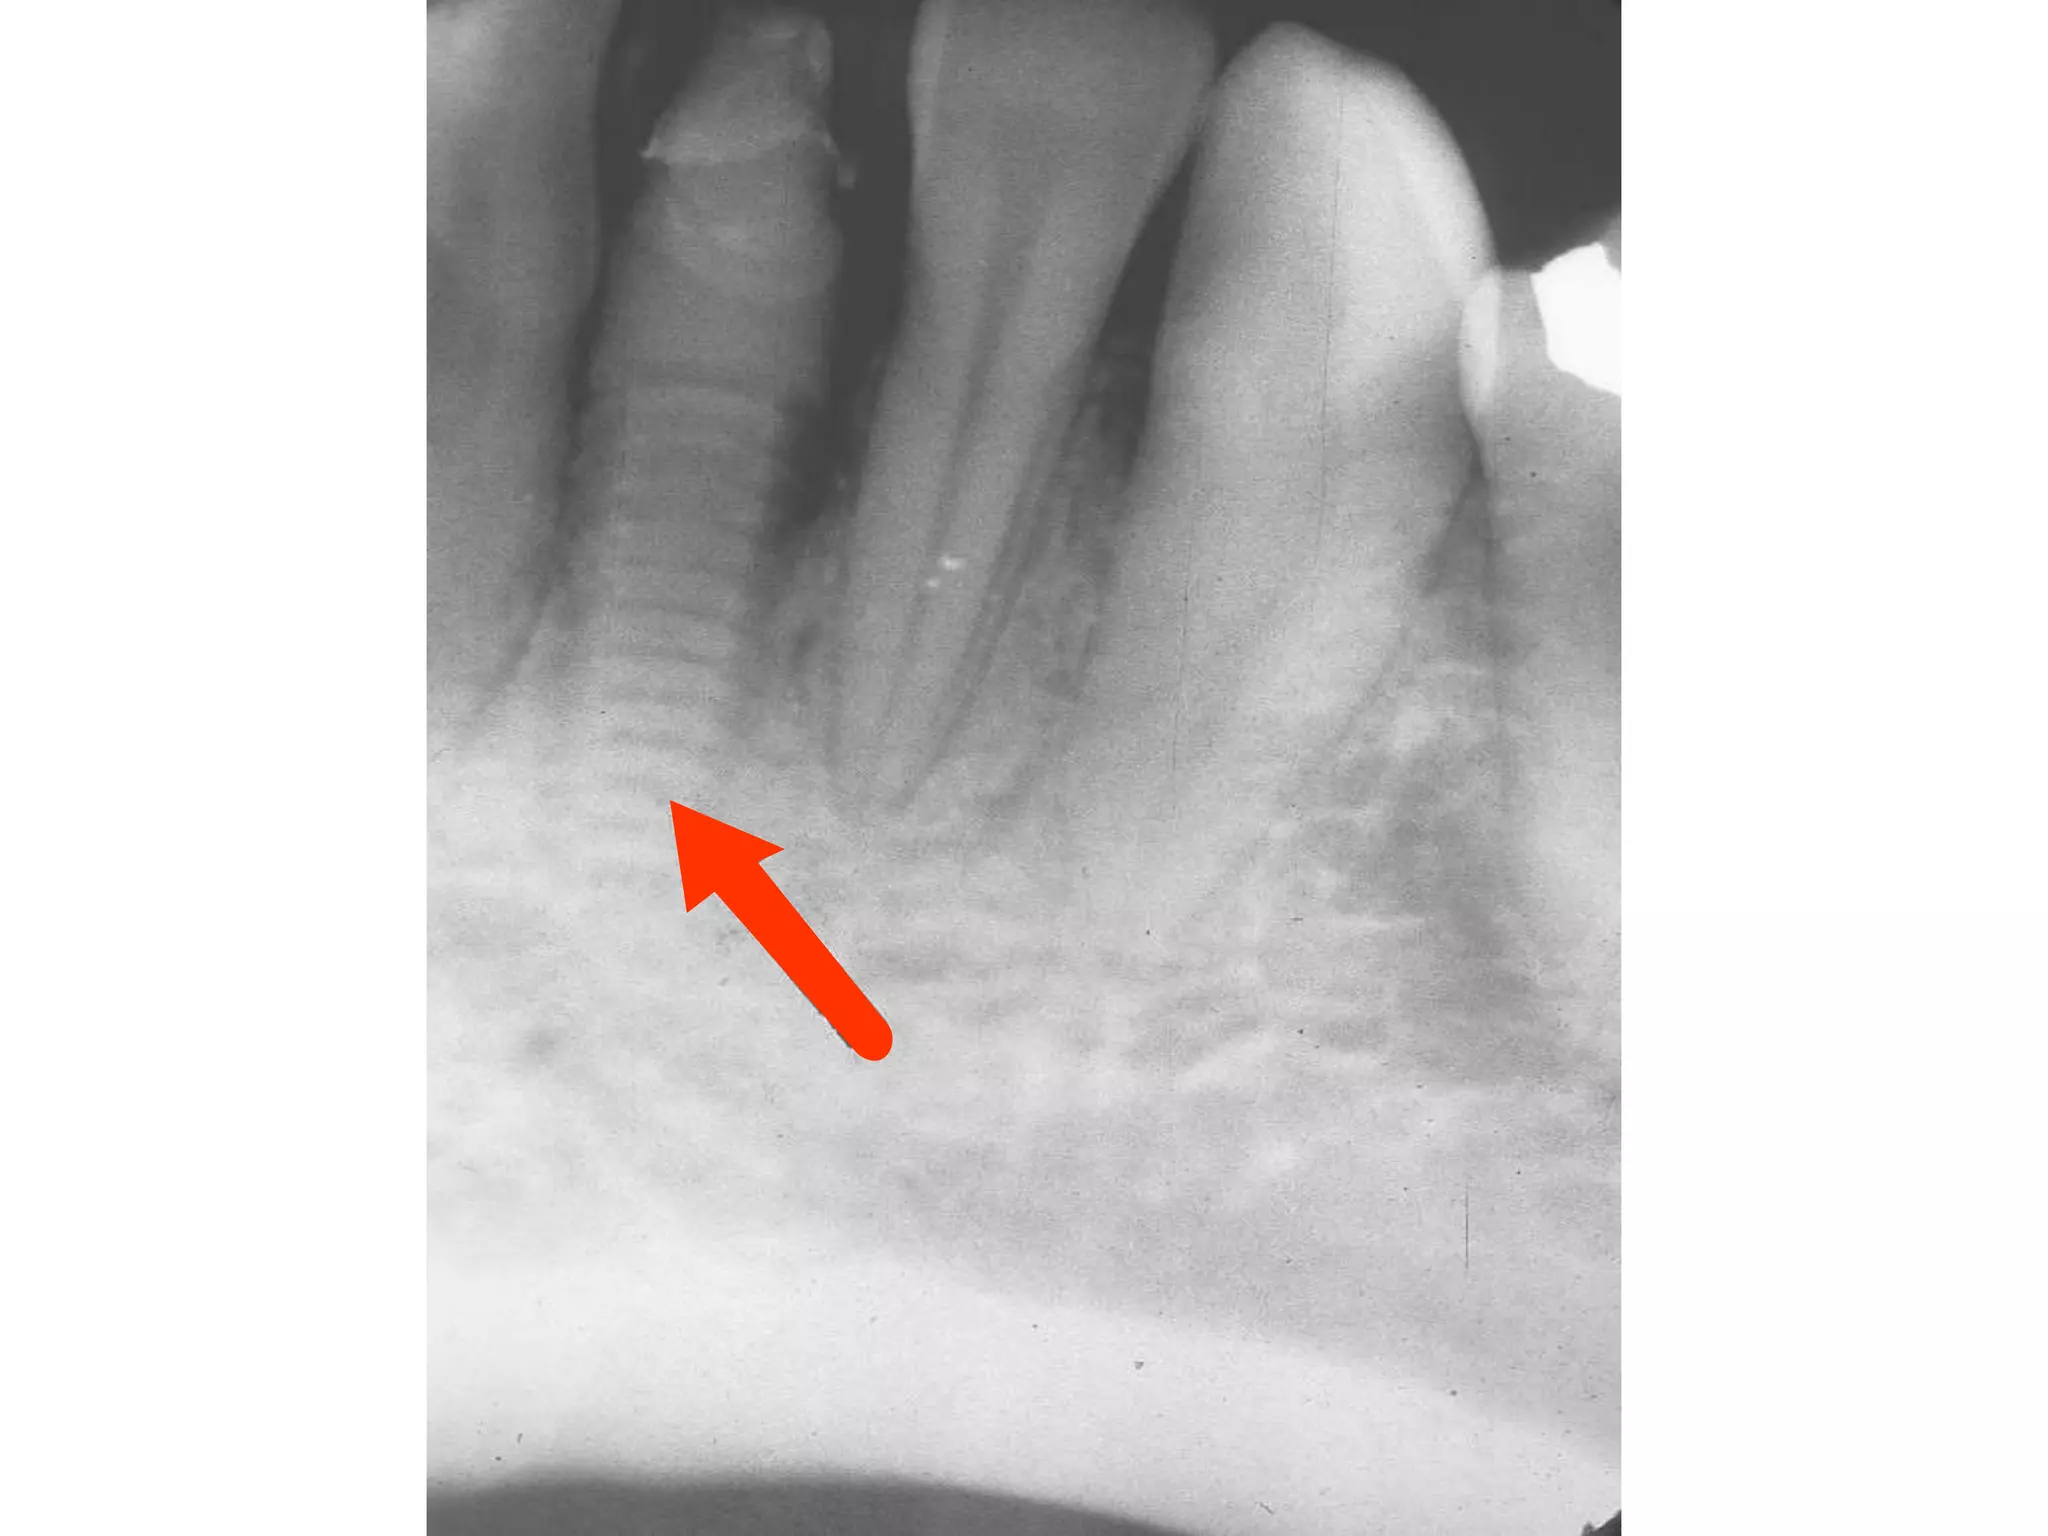

Severe Adult Periodontitis

Tooth mobility

Extensive horizontal bone

loss or vertical osseous

defects

Furcation involvement

Severe adult

periodontitis